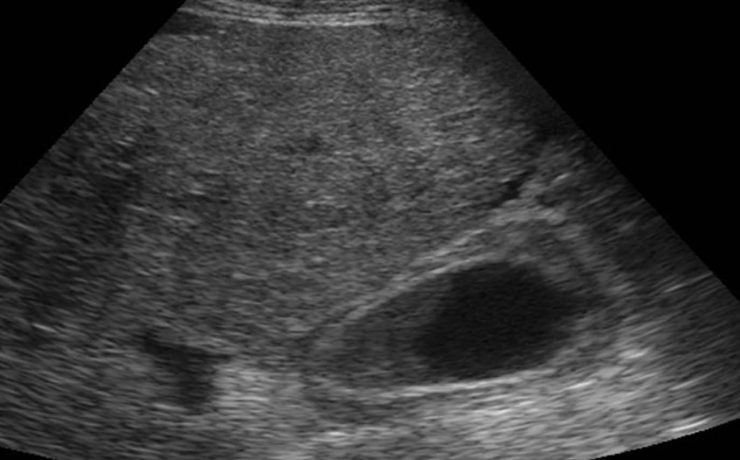

LA IMPORTANCIA DE LA ECOGRAFIA A LAS 11+0 A 13+6 SEMANAS DE EMBARAZO

Al principio, el ultrasonido en el primer trimestre se empezó a utilizar para medir la longitud cráneo-caudal del feto y estimar la edad gestacional, pero actualmente, además de eso, se evalúan varios detalles que permiten hacer una evaluación completa para identificar factores de riesgo que compliquen la gestación. Los objetivos